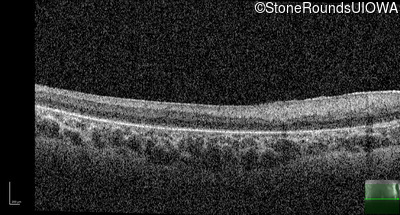

Optical Coherence Tomography - Right - No Light Perception

Exemplar / OCT Stack

Optical Coherence Tomography - Left - No Light Perception